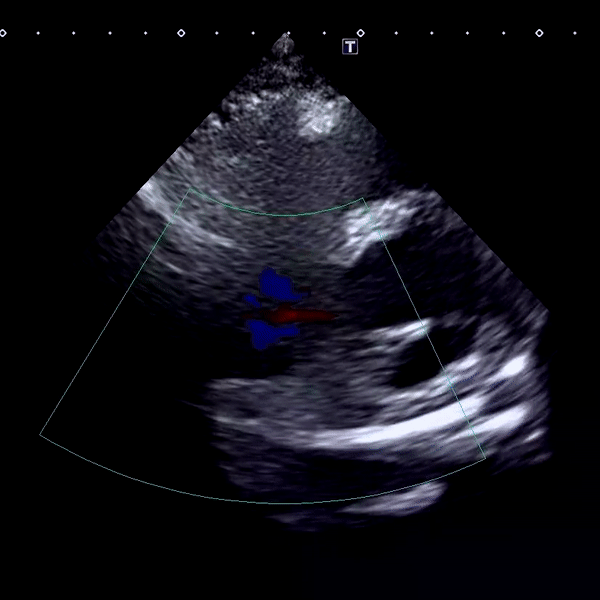

심비대(심장비대증는 말 그대로 심장이 정상보다 커진 상태를 의미합니다. 크게 두 가지 형태로 나눌 수 있습니다:

심비대는 여러 원인으로 발생할 수 있습니다. 가장 중요한 건 원인을 정확히 파악하고 그에 맞는 치료를 시작하는 것입니다.

판막질환

심근질환(심근병증)